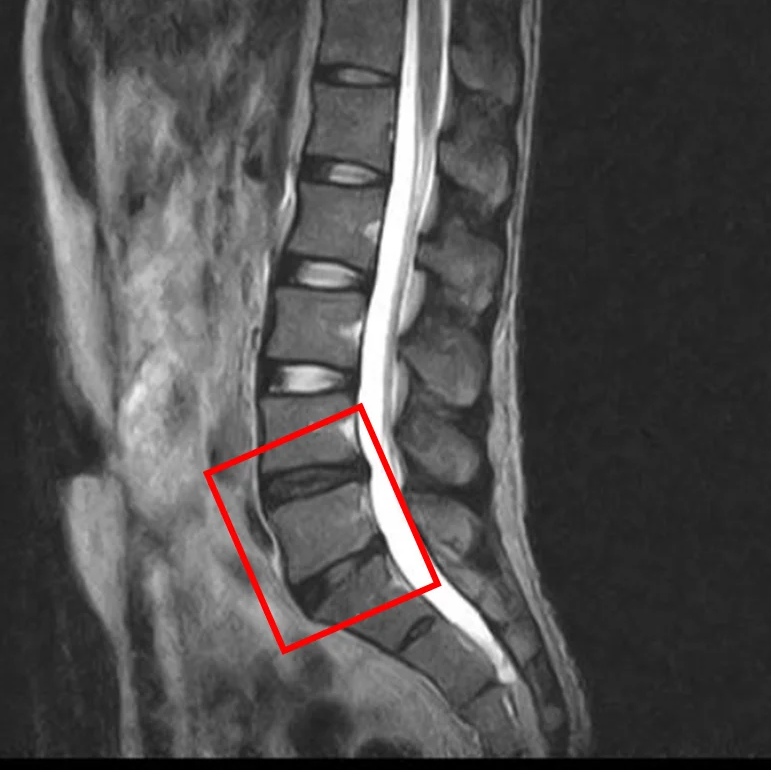

По данным МРТ и результатам осмотра пациента выявлена дегенерация и грыжа межпозвоночных дисков L4/L5, L5/S1.

Симптомы по 10-балльной шкале (0 – отсутствие симптомов, 10 – сильные боли/онемение):

– боли в пояснице: 5;

– боли в ногах: 5;

– онемение в ногах: 3;

– боли в ягодицах: 4.